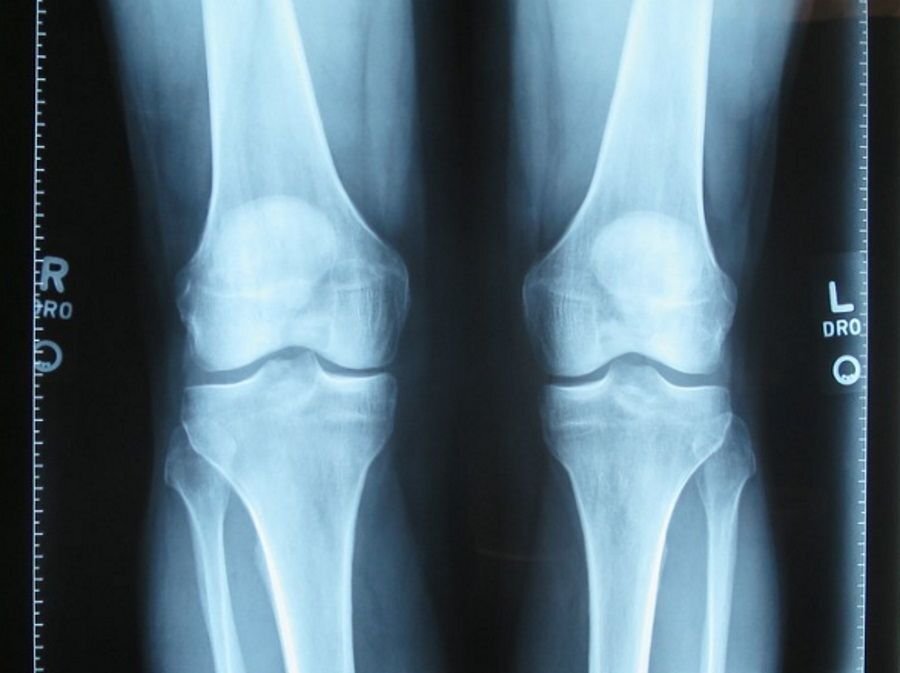

Когда мы двигаемся, наши колени фактически... вращаются. Этот вывод является следствием инновационной модели трения, представленной учеными из Быдгощского технологического университета. Модель может быть использована в медицине и машиностроении, заявили в университете.

По мнению исследователей из Института математики и физики Быдгощского технологического университета, Яна и Енджея Снядецки (PBŚ), модель может помочь в создании методов лечения снижения эффективности опорно-двигательного аппарата человека. Если выводы из модели можно перенести в мир механических устройств, то по крайней мере в некоторых случаях трение скольжения можно преобразовать в трение качения. Помимо энергетической выгоды, это должно увеличить долговечность взаимодействующих элементов конструкции.

- Гипотеза о существовании в наших суставах трения качения, действующего в мезомасштабе, на уровне мицеллярных структур, впервые была высказана 15 лет назад. Теперь нам удалось преобразовать ее в модель, учитывающую важнейшие физико-химические процессы, происходящие в синовиальной жидкости, заполняющей полости суставов, и на поверхностях обоих трущихся хрящей, — говорит проф. доктор хаб. англ. Адам Гадомски, один из авторов статьи, опубликованной в «Journal of Physics D: Applied Physics» ( DOI: 10.1088/1361-6463/ac90d1 ).

Человеческие суставы как подшипники машин

Как пояснил исследователь, цитируемый в пресс-релизе, синовиальная жидкость играет роль тонкого слоя смазки. Она разъединяет трущиеся части костей, покрытые хрящами, в пределах суставов. Жидкость состоит в основном из воды с небольшим количеством биополимеров (в основном гиалуроновой кислоты), фосфолипидов и белков. Эти компоненты являются критически важными и взаимодействуют друг с другом сложным образом, который до сих пор не до конца изучен учеными.